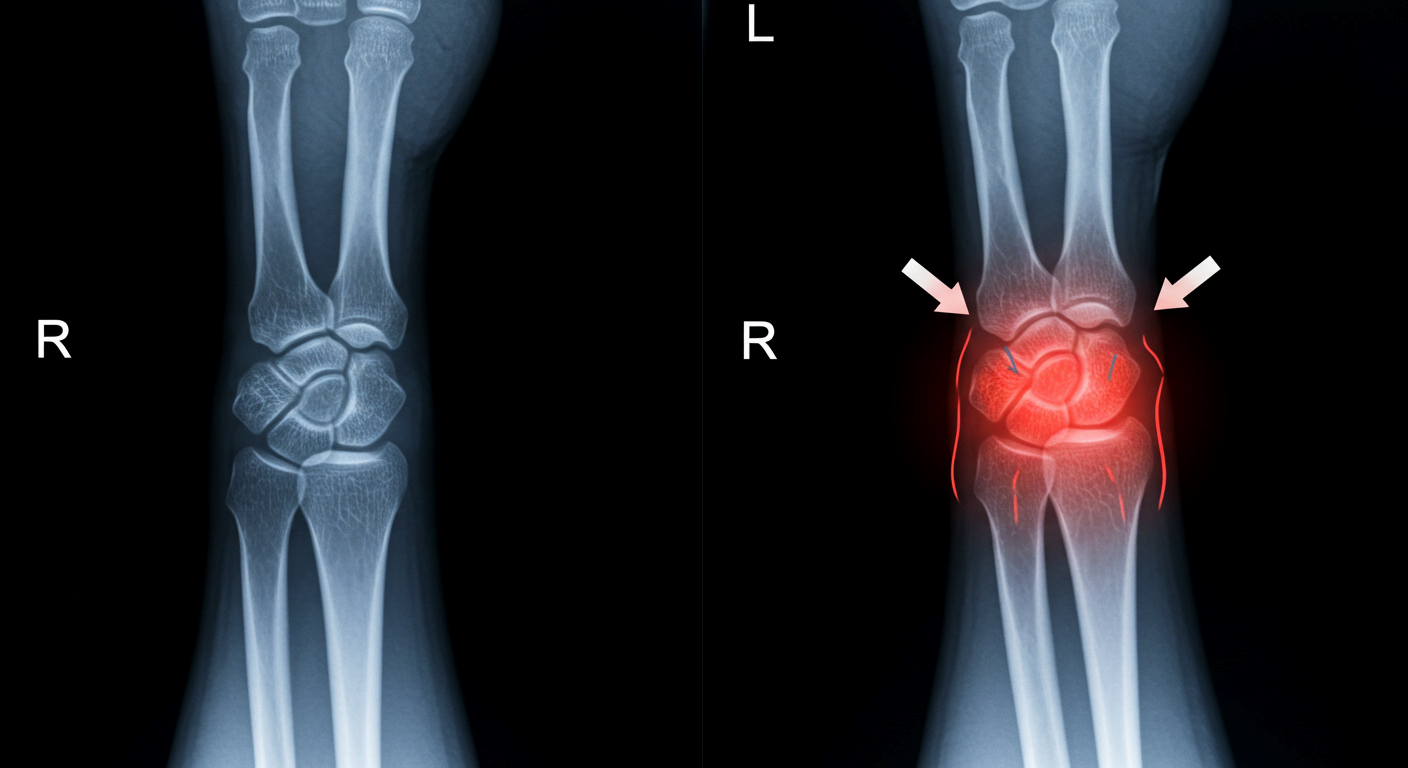

3. 관절염

나이가 들면서 손목 관절의 연골이 닳고 뼈끼리 부딪히면서 퇴행성 관절염이 생길 수 있습니다. 또한 류마티스 관절염처럼 면역 시스템이 손목 관절을 공격하는 질환도 통증의 원인이 될 수 있습니다.

4. 손목 부상과 외상

운동 중 넘어지면서 손을 짚거나, 무거운 물건을 들다 손목이 꺾이는 등의 외상은 골절, 인대 손상, 염좌 등을 유발합니다. 부상 초기에는 단순 타박상처럼 보여도, 시간이 지나면서 통증이 지속되거나 악화될 수 있습니다.